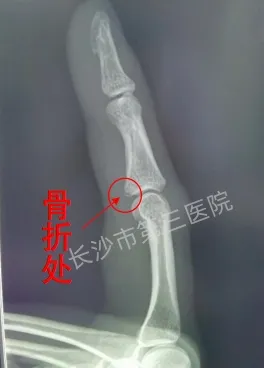

骨折

X光